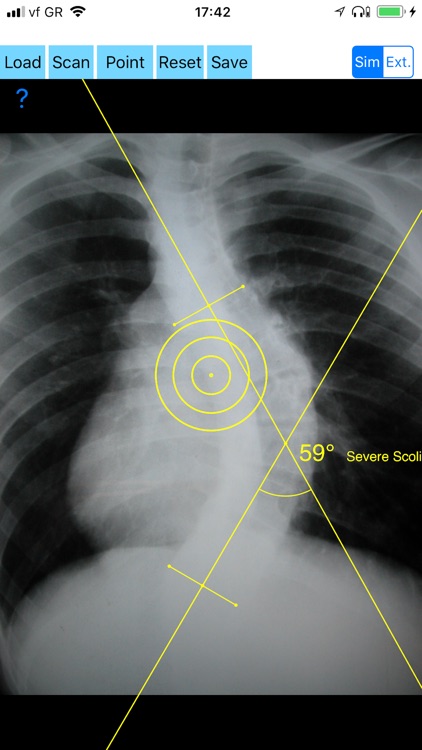

Cobb method is considered the standard for measuring curve size in scoliosis. Cobb angles are always measured from the superior end plate of the most cephalad end vertebra to the inferior end plate of the most caudal end vertebra in the curve. Meticulous line drawings and precise measurements is paramount importance in order to quantify the magnitude of spinal deformities and monitor the success or failure of treatment for scoliosis.

-Offers a very convenient way to determine the most accurate possibly way at once. By marking four points at the same X-ray, at each spine the App calculates the Cobb angle. In cases where values are out of normal ranges, the scoliosis is categorized according to measured angle as mild, moderate, severe. To simplify the process and to minimize inter-observer errors usually by not selecting the actual end vertebra, the app offers also in ext mode the ability to draw the vertical reference line through the patient’s sacrum and to identify more easily the end vertebrae s (ext method).